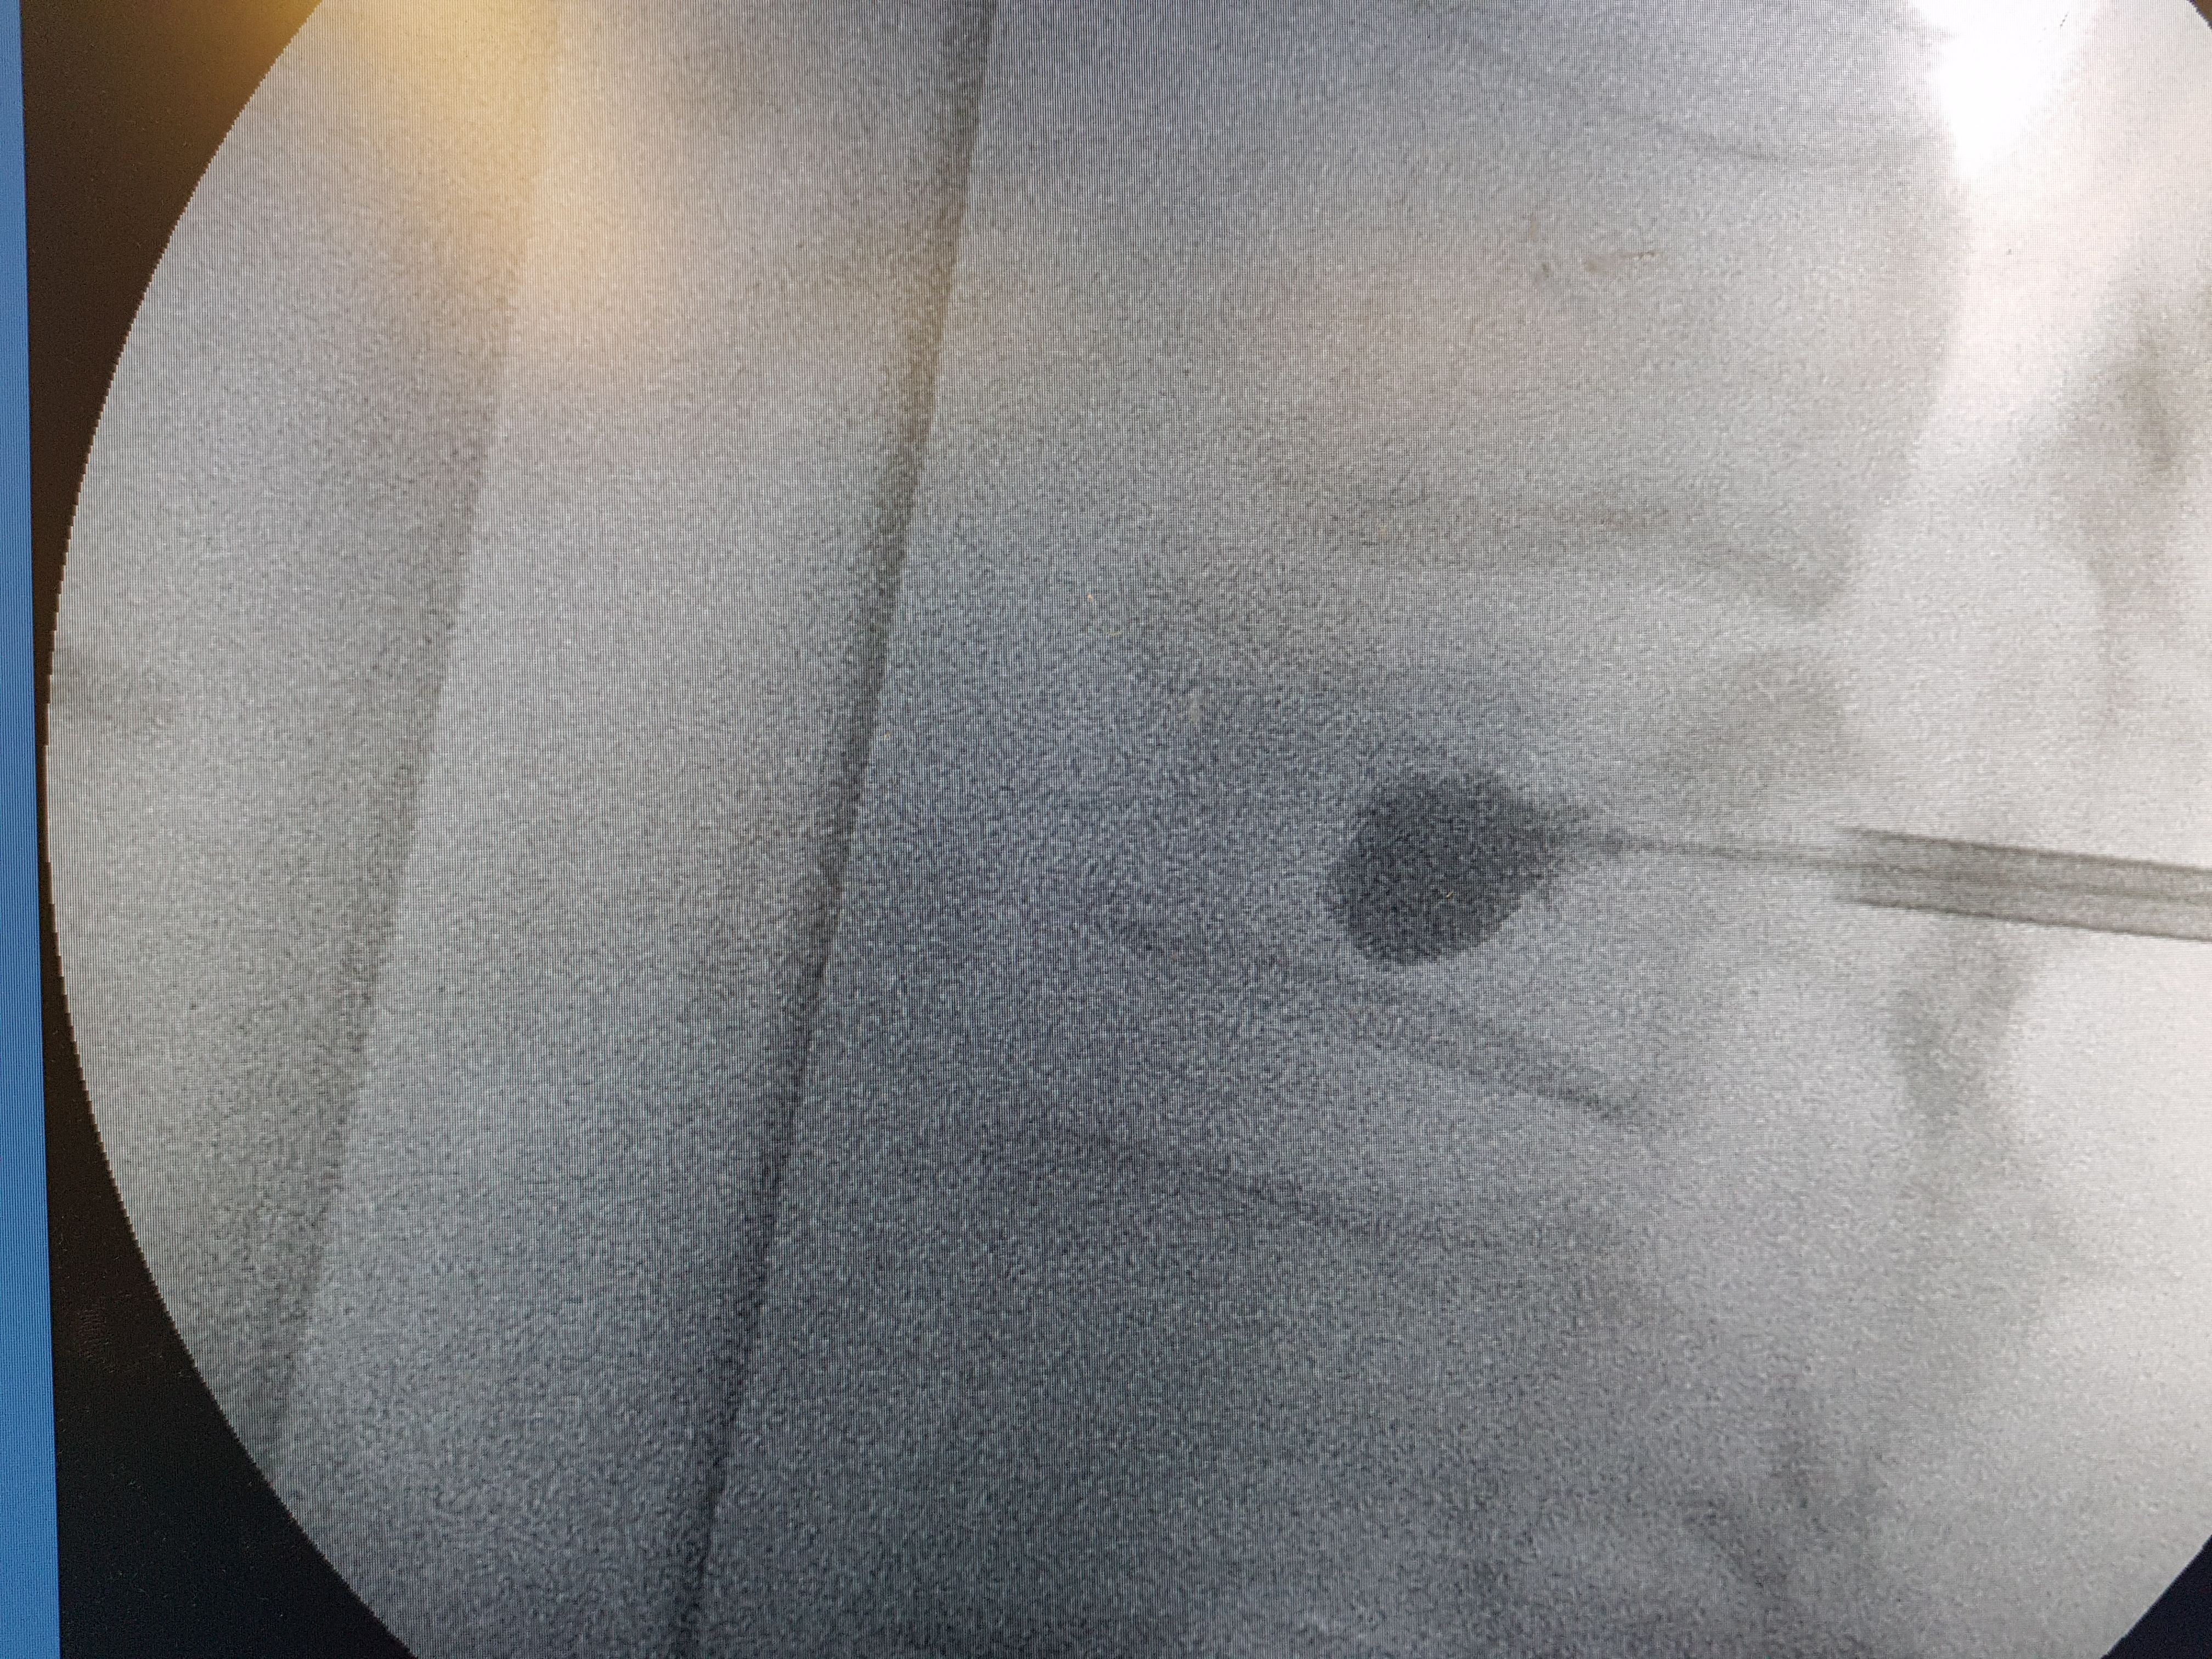

It is a minimally invasive technique with a 3 mm skin incision in which a balloon is inserted and creates a cavity in the fractured vertebra. A special material (PMMA) is then injected into the vertebra , restoring its morphology and passing the pain. The procedure takes 30-45 min and the patient is mobilized the same day. Usually the elimination of pain is immediate. The same operation is also indicated in cases of vertebral fractures from myeloma or other tumours (metastatic disease). The probability of complications is considered very low 1-4%. In the following photos you can see the procedure of balloon dilation in the vertebra and the subsequent injection of the sclerosing material.

Intraoperative radiograph with the sclerosing material injected into the vertebra and restored to its shape.